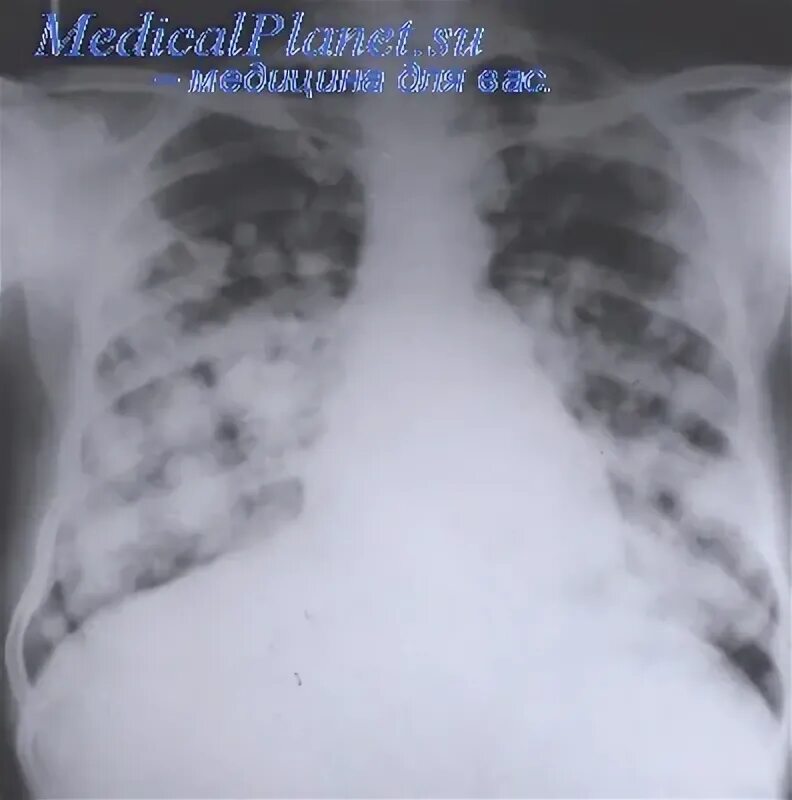

Единичные метастазы в легких